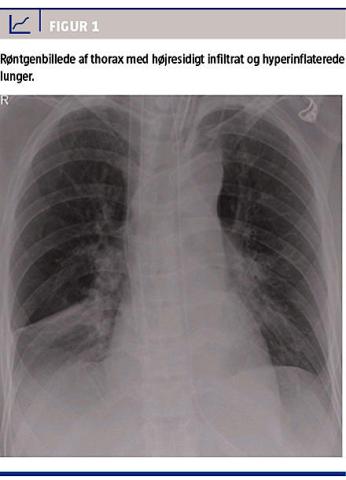

niveauet. En røntgenundersøgelse af thorax viste hyperinflaterede lunger og et højresidigt infiltrat (Figur 1). Man påbegyndte empirisk antibiotisk behandling med cefuroxim pga. leukocytose og et C-reaktivt proteinniveau på 67 mg/l. Efter 12 timer blev patienten atter svært bronkospastisk og hypotensiv. Da ventilation med et toptryk på 40 cm H2O og en frekvens på 10 kun gav små tidalvolumina og hypotension, forsøgte man håndventilation med sevofluran og adrenalininfusion (0,2 mikrogram/kg/min), men PaCO2-niveauet steg til 22 kPa med en pH på 6,90.